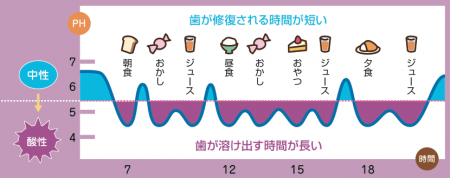

口腔内は通常は弱アルカリ性から中性(pH6.7)状態を保っており、食事をするたびに口腔内が酸性状態に傾きます。歯が溶ける境目はpH5.5以下になると言われています。

口腔内が酸性状態になると歯の表面のミネラル成分が溶かされ始めます(脱灰)。40分ほど時間が経つと唾液の自浄作用により口腔内が中性状態に戻り、溶かされた歯の成分が元に戻ろうとします(再石灰化)。そのため再石灰化をすれば歯が虫歯になることはありません

しかし、pH5.5以下の状態が長く続くような食生活を続けていると・・・

歯が溶け出す時間が長いため、歯に穴があく虫歯ができてしまいます。歯に穴があくと再石灰化することは不可能なため、歯科治療する方法しかありません

食事や間食は規則正く決まった時間にとるようにしましょう